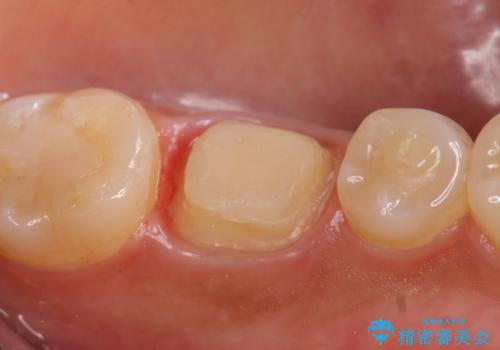

その後症状の緩解を確認後、オールセラミッククラウンによる補綴を行いました。

- オールセラミッククラウン…¥100,000、仮歯…¥10,000、ファイバーコア…¥20,000費用は治療当時の料金となります